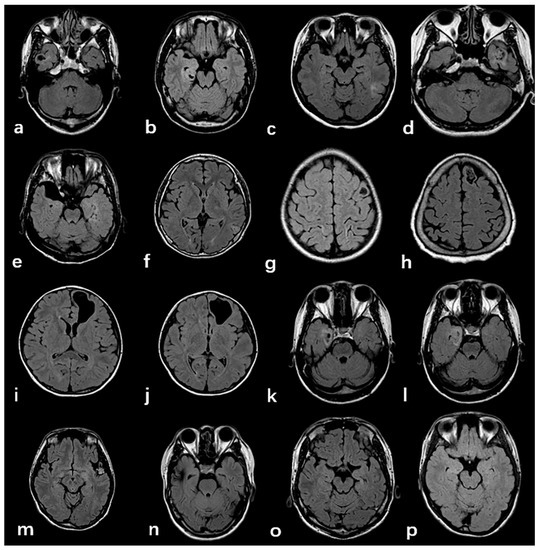

3.2. Radiologic and Pathology Findings

| MRI features of FCD | 0.680 | |||

| Cortex atrophy/thickening | 90 (13.5%) | 59 (13.4%) | 31 (13.8%) | |

| Indistinctness of the gray–white matter junction | 176 (66.2%) | 118(65.9%) | 58 (66.7%) | 1.000 |

| Intensity | 166 (62.4%) | 116 (64.8%) | 50 (57.5%) | 0.281 |

| MRI Negative | 36 (13.5%) | 19 (10.6%) | 17 (19.5%) | 0.056 |